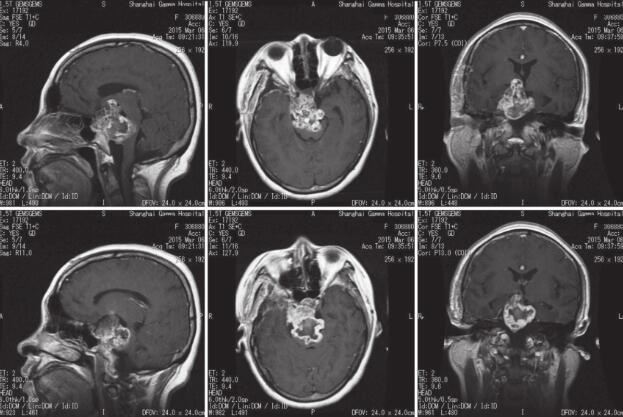

患者于2014年9月15日出现突发头痛伴恶心呕吐,伴双眼复视,就诊外院查头CT诊断蛛网膜下隙出血,当地医院住院对症支持治疗后患者头痛及复视症状消失,患者具体诊疗过程不能回忆。2014年9月16日患者进一步查头颅MRI提示鞍上区占位,T1低信号T2高信号,明显均匀强化,外院建议定期随访。患者于2个月前开始出现右眼睑下垂及行走不稳,就诊我院。头颅MRI提示:鞍上可见异常信号肿块影,T1WI低信号,T2WI高信号,增强后混杂增强信号,CT提示病灶钙化(图1)。回忆本次病程,患者无明显头痛及恶心呕吐,无复视,无四肢活动障碍。

图1 2015-2术前影像学检查

鞍上可见异常信号肿块影,MR T1WI低信号,T2WI高信号,增强后混杂增强信号,CT提示病灶钙化